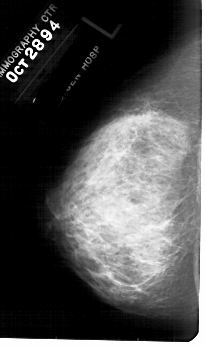

A_1781_1.LEFT_CC

LEFT_CC LINES 5191 PIXELS_PER_LINE 3061 BITS_PER_PIXEL 12 RESOLUTION 43.5 NON_OVERLAY